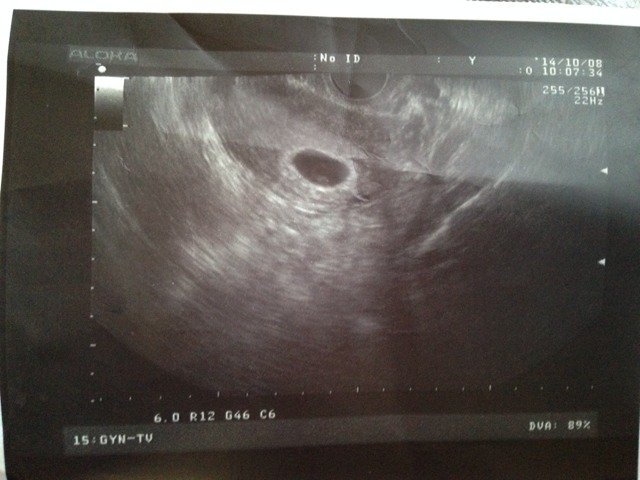

我的宝宝还有救没?明白的朋友帮帮忙,我是做的移植9.2号移植的,今天10.8号去看胎心,没有,医生说胎芽太小让下个星期在去看,心里超级没底!害怕极了!有和我同样情况的吗?

您好,你的情况宝宝是有救的,一般怀孕30—40天形成的是胎囊,40—50天形成的是胎芽,50—60天形成胎心,注意复查就可以了。

没事,在过几天去看去,我36天的时候去看医生,医生说没有胎心和胎芽,我的心情和你一样,很害怕,我就等到两个月的时候去看了一下,宝宝没事了,什么都正常了。

过几天看看吧,40多天就应该有胎心管拨动了